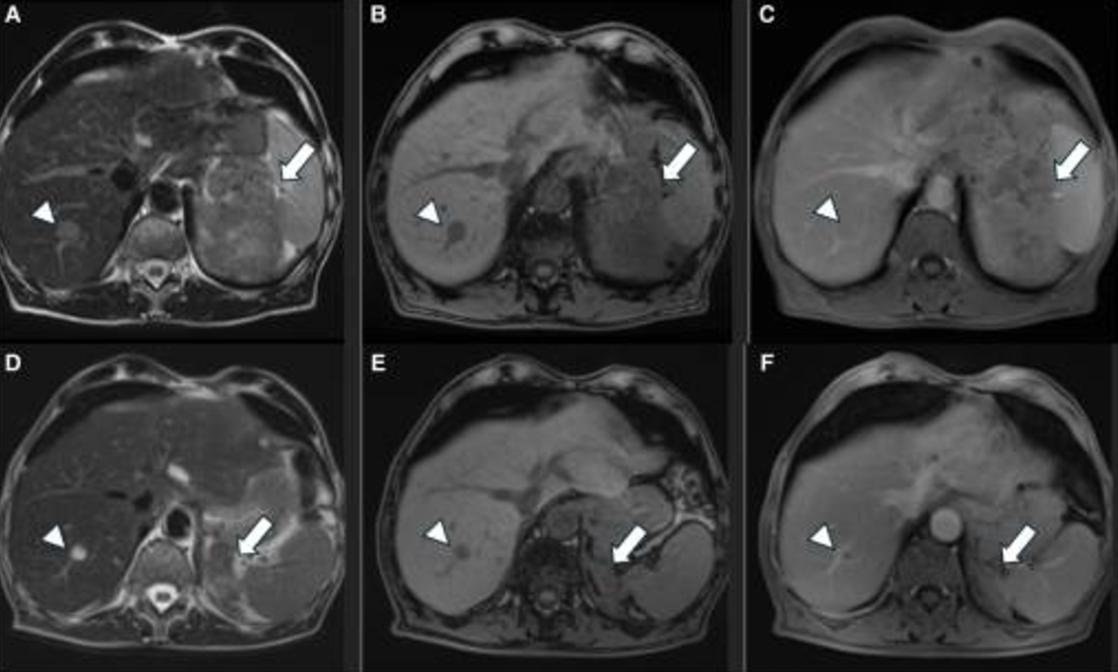

MRI证实存在增大的不均匀左肾上腺肿块,并伴有强烈的对比增强(图3A-3C)。此外,肝脏中描述了2个新的可疑病变,其中1个在第VIII段为2cm,另一个在第VI段为7.7mm,倾向于转移性疾病(图3A-3C)。胸部CT还显示了多个继发性双侧肺部病变(图4A)。18FDG-PET显示,肾上腺病变(18SUVmax)、肝和肺病变(10-12SUVmax)和左肾上腺静脉(12SUVmix)的摄取增加,与血管血栓一致(图2)。

图3 同一患者治疗前和治疗后6个月的MRI。治疗前轴向T2W STIR(A)、T1反相(B)和对比增强T1W SPIR(C)图像显示,左侧肾上腺存在异质性肿块(A和B中的箭头),并具有强烈的对比增强(C中的箭头。右肝叶也可见肝转移(A-C中的箭头)。相应的治疗后MRI显示肾上腺病变大小显著减小(D-F中的箭头)。注意对比后图像上病变的最小增强(F中的箭头),这是肿瘤对治疗反应的另一个发现。在治疗后MRI上,肝脏病变也减少(D和E中的箭头),增强程度较低(F中的箭头)

两种治疗后3个月的成像显示,所有病变都有部分反应,6个月时,根据RECIST 1.1标准,肾上腺和肝脏病变有进一步的部分反应(图3D-3F),肺转移完全消失(图4B)。患者在ACC诊断后8个月仍然活着,仅继续接受米托坦治疗。